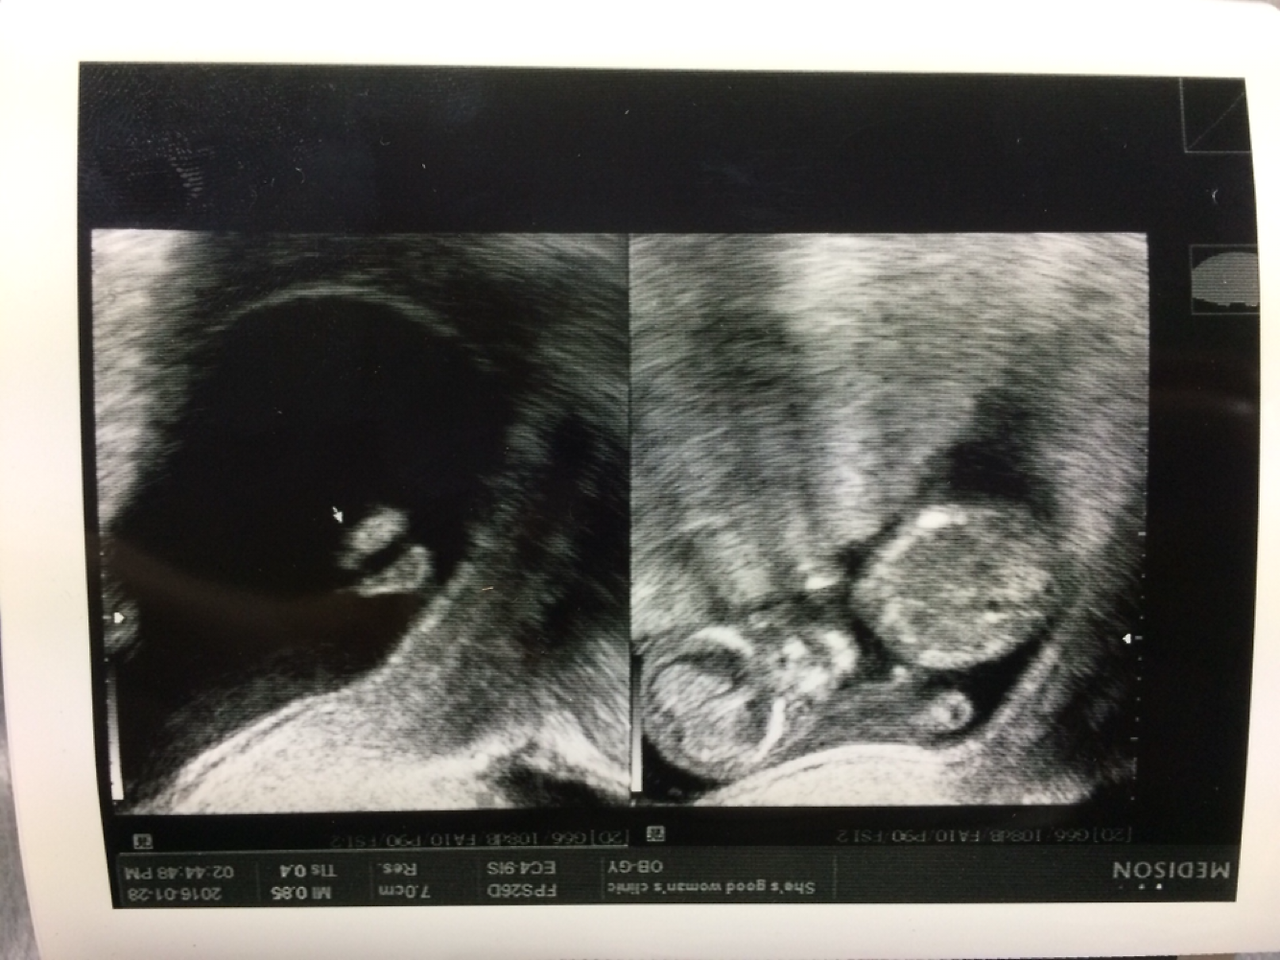

임신 12주

한파로 인해 추위와 맞서 싸우는 것도 힘들었던 겨울. 하지만 이사한 지 한 달도 안 된 집에선 수도가 얼고, 보일러까지 말썽을 피웠으며 예상치 못한 결로현상으로 인해 집에 곰팡이까지 생기는 최악의 나날들이 나의 임신 12주 차를 맞이하게 했다. 한마디로 스트레스 지수가 최고점을 찍고 우주로 날아간 상황. 그런데 나의 이런 스트레스와는 상관없이 아이는 2주 전 보다 많이 컸다고 의사 선생님께서는 말씀하셨다.

이젠 발가락도 보이고 얼굴도 제법 보인다. 아직 살이 없어서 그런지 얼굴은 약간 외계인처럼 보이긴 했지만 그래도 너무 잘 커주고 있는 아이를 보니 2주 동안 받았던 스트레스가 사르르 풀리는 듯했다. 그리고 임신 11주가 되면 기형아 검사를 하는데 다행히 아이는 (초음파로는) 정상이라는 결과가 나왔다. 그리고 나는 또 다른 검사를 위해 피를 뽑고 산부인과를 나왔다. 임신을 하고 나서 얼마나 많은 피를 뽑는지 모른다.(갑상선 호르몬 수치가 높아서 한 달에 한 번씩 피를 뽑고 있던 중) 안 그래도 철분 부족이라 했는데...